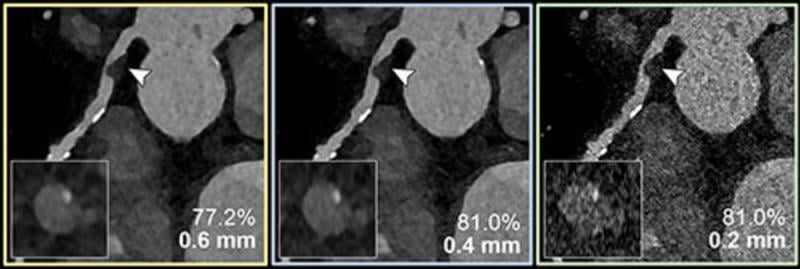

“The study used a combination of artificial vessel models and real-world patient data,” Dr. Emrich said. “It simulated three types of reconstructions from a single PCD-CT scan, resembling conventional CT, high-resolution, and ultrahigh-spatial-resolution scans. Observers evaluated the severity of stenosis and generated CAD-RADS classifications, guiding further patient management decisions.”

In-vitro results demonstrated a reduced overestimation of the stenosis by ultrahigh-spatial-resolution scans by reducing the adverse effects of the calcifications on the image.

Results from the patients with suspected or diagnosed coronary artery disease confirmed a lower median degree of stenosis for calcified plaques (29% vs. 42%) with ultrahigh-spatial-resolution PCD-CT compared to standard CT. Ultrahigh-spatial-resolution often led to patients being reclassified to a lower CAD-RADS category. Of the 114 patients, 54% were given a lower CAD-RADS classification than they were originally assigned. The researchers found in-vitro quantification of the 193 coronary CT angiography-based stenoses was also more accurate using ultrahigh-spatial-resolution than standard resolution.

Dr. Emrich explained that ultrahigh-spatial-resolution may address the current limitations of conventional cardiac CT angiography by reducing the overestimation of stenosis due to calcium blooming, an effect which can cause small, high-density structures—such as calcifications—to appear larger than their true size.